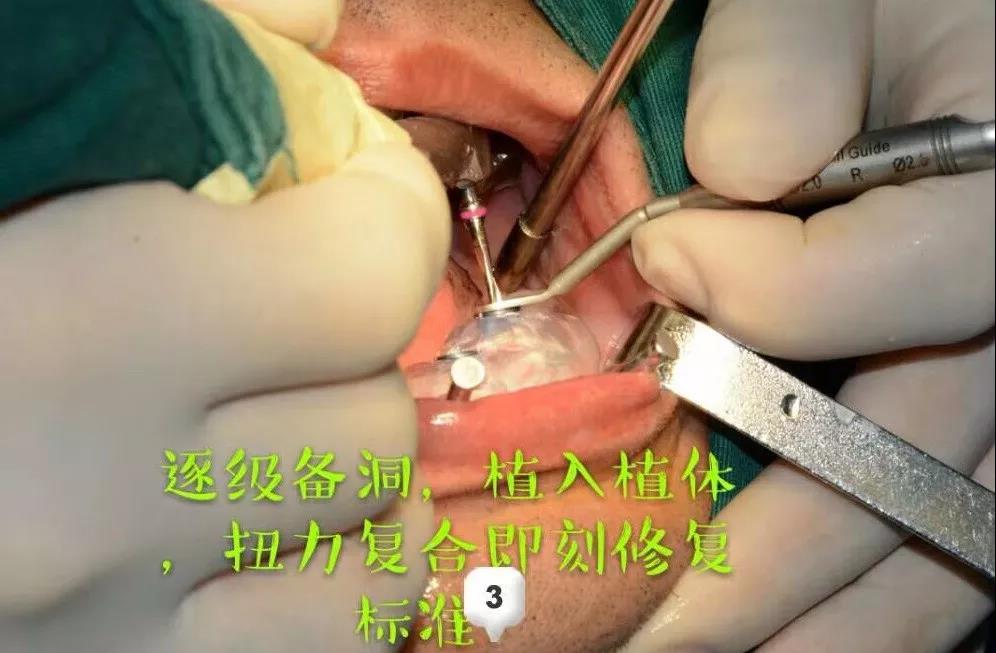

ЁЁЁЁЪЅНрПкЧЛгРаЫТЗдКжжжВПЦЕФВмН№ЗхжїШЮЮЊМжЯШЩњжЦЖЈСЫМДАЮМДжжЕФжжжВЗНАИЃЌдкАЮГ§ЛМбРЕФЭЌЪБжВШыжжжВЬхЃЌВЩгУALL-ON-6ШЋПкжжжВММЪѕХфКЯ3DДђгЁММЪѕКЭЪ§зжЛЏжжбРЕМАхЃЌШЋПкжжжВМгЩЯМДПЬИКжиЃЌЪЧЗЧГЃгааЇЕФбРСажиНЈЗНАИЁЃ

ЁЁЁЁЕквЛДЮКФЪБСНИіЖраЁЪБЃКЯШНјааСЫЪѕЧАЕФВтСПЦРЙРЃЌжИЖЈЪжЪѕЗНАИ;ЪѕжаВЩгУЪ§зжЛЏжжбРЕМАхЃЌОЋзМЖЈЮЛ;ж№МЖБИЖДЃЌжВШыжВЬхЃЌХЄСІИДКЯЭъГЩжВШыЩЯАыПкЁЃ

ЁЁЁЁОЙ§вЛжмЕФЛжИДЪБМфЃЌНјааСЫЯТАыПкЕФжжжВЃЌВмжїШЮСЊКЯжжжВЬхМгЙЄГЇЕФММЪІИЯЙЄжЦзїЭъГЩСЫШЋПкЮобРђЂЕФМДПЬаоИДЃЌРњЪБ12ИіаЁЪБЃЌЪжЪѕНсЪјЪБвбОЪЧЭэЩЯ10ЕуЖрЃЌЛМепгжПЊГЕИЯЛиСЫББОЉЁЃ